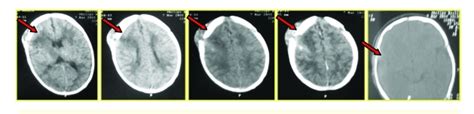

Diastatic fractures occur along the suture lines and usually affect newborns and infants in whom suture fusion has not yet occurred. Diastatic fractures occur in the pediatric population. Line involves separation of one or more cranial.

Diastatic fractures occur across the line of a skull suture, pushing the bony plates apart. Browse the use examples 'diastatic skull fracture' in the great english corpus. Skull base fractures are of high importance in neurotrauma. Check out the pronunciation, synonyms and grammar. In adults, a diastatic fracture severely affects the lambdoidal suture. As with most traumas, other injuries should be suspected and before transporting a patient immobilization. Separation of sutures due to blow with blunt weapon or from ce… Diastatic fractures occur along the suture lines and usually affect newborns and infants in whom suture fusion has not yet occurred. Due to the trauma, diastatic. It is a closed diastatic skull fracture normally observed in children less. In this type of fracture, the normal suture lines are widened. A diastatic skull fracture takes place along the suture lines of the skull. Diastatic fractures occur in the pediatric population. Its shape indicate… diastatic fracture. Best diastatic skull fractures products. Two areas of scalp hematoma. While this type of fracture is usually seen in infants and young children as the.